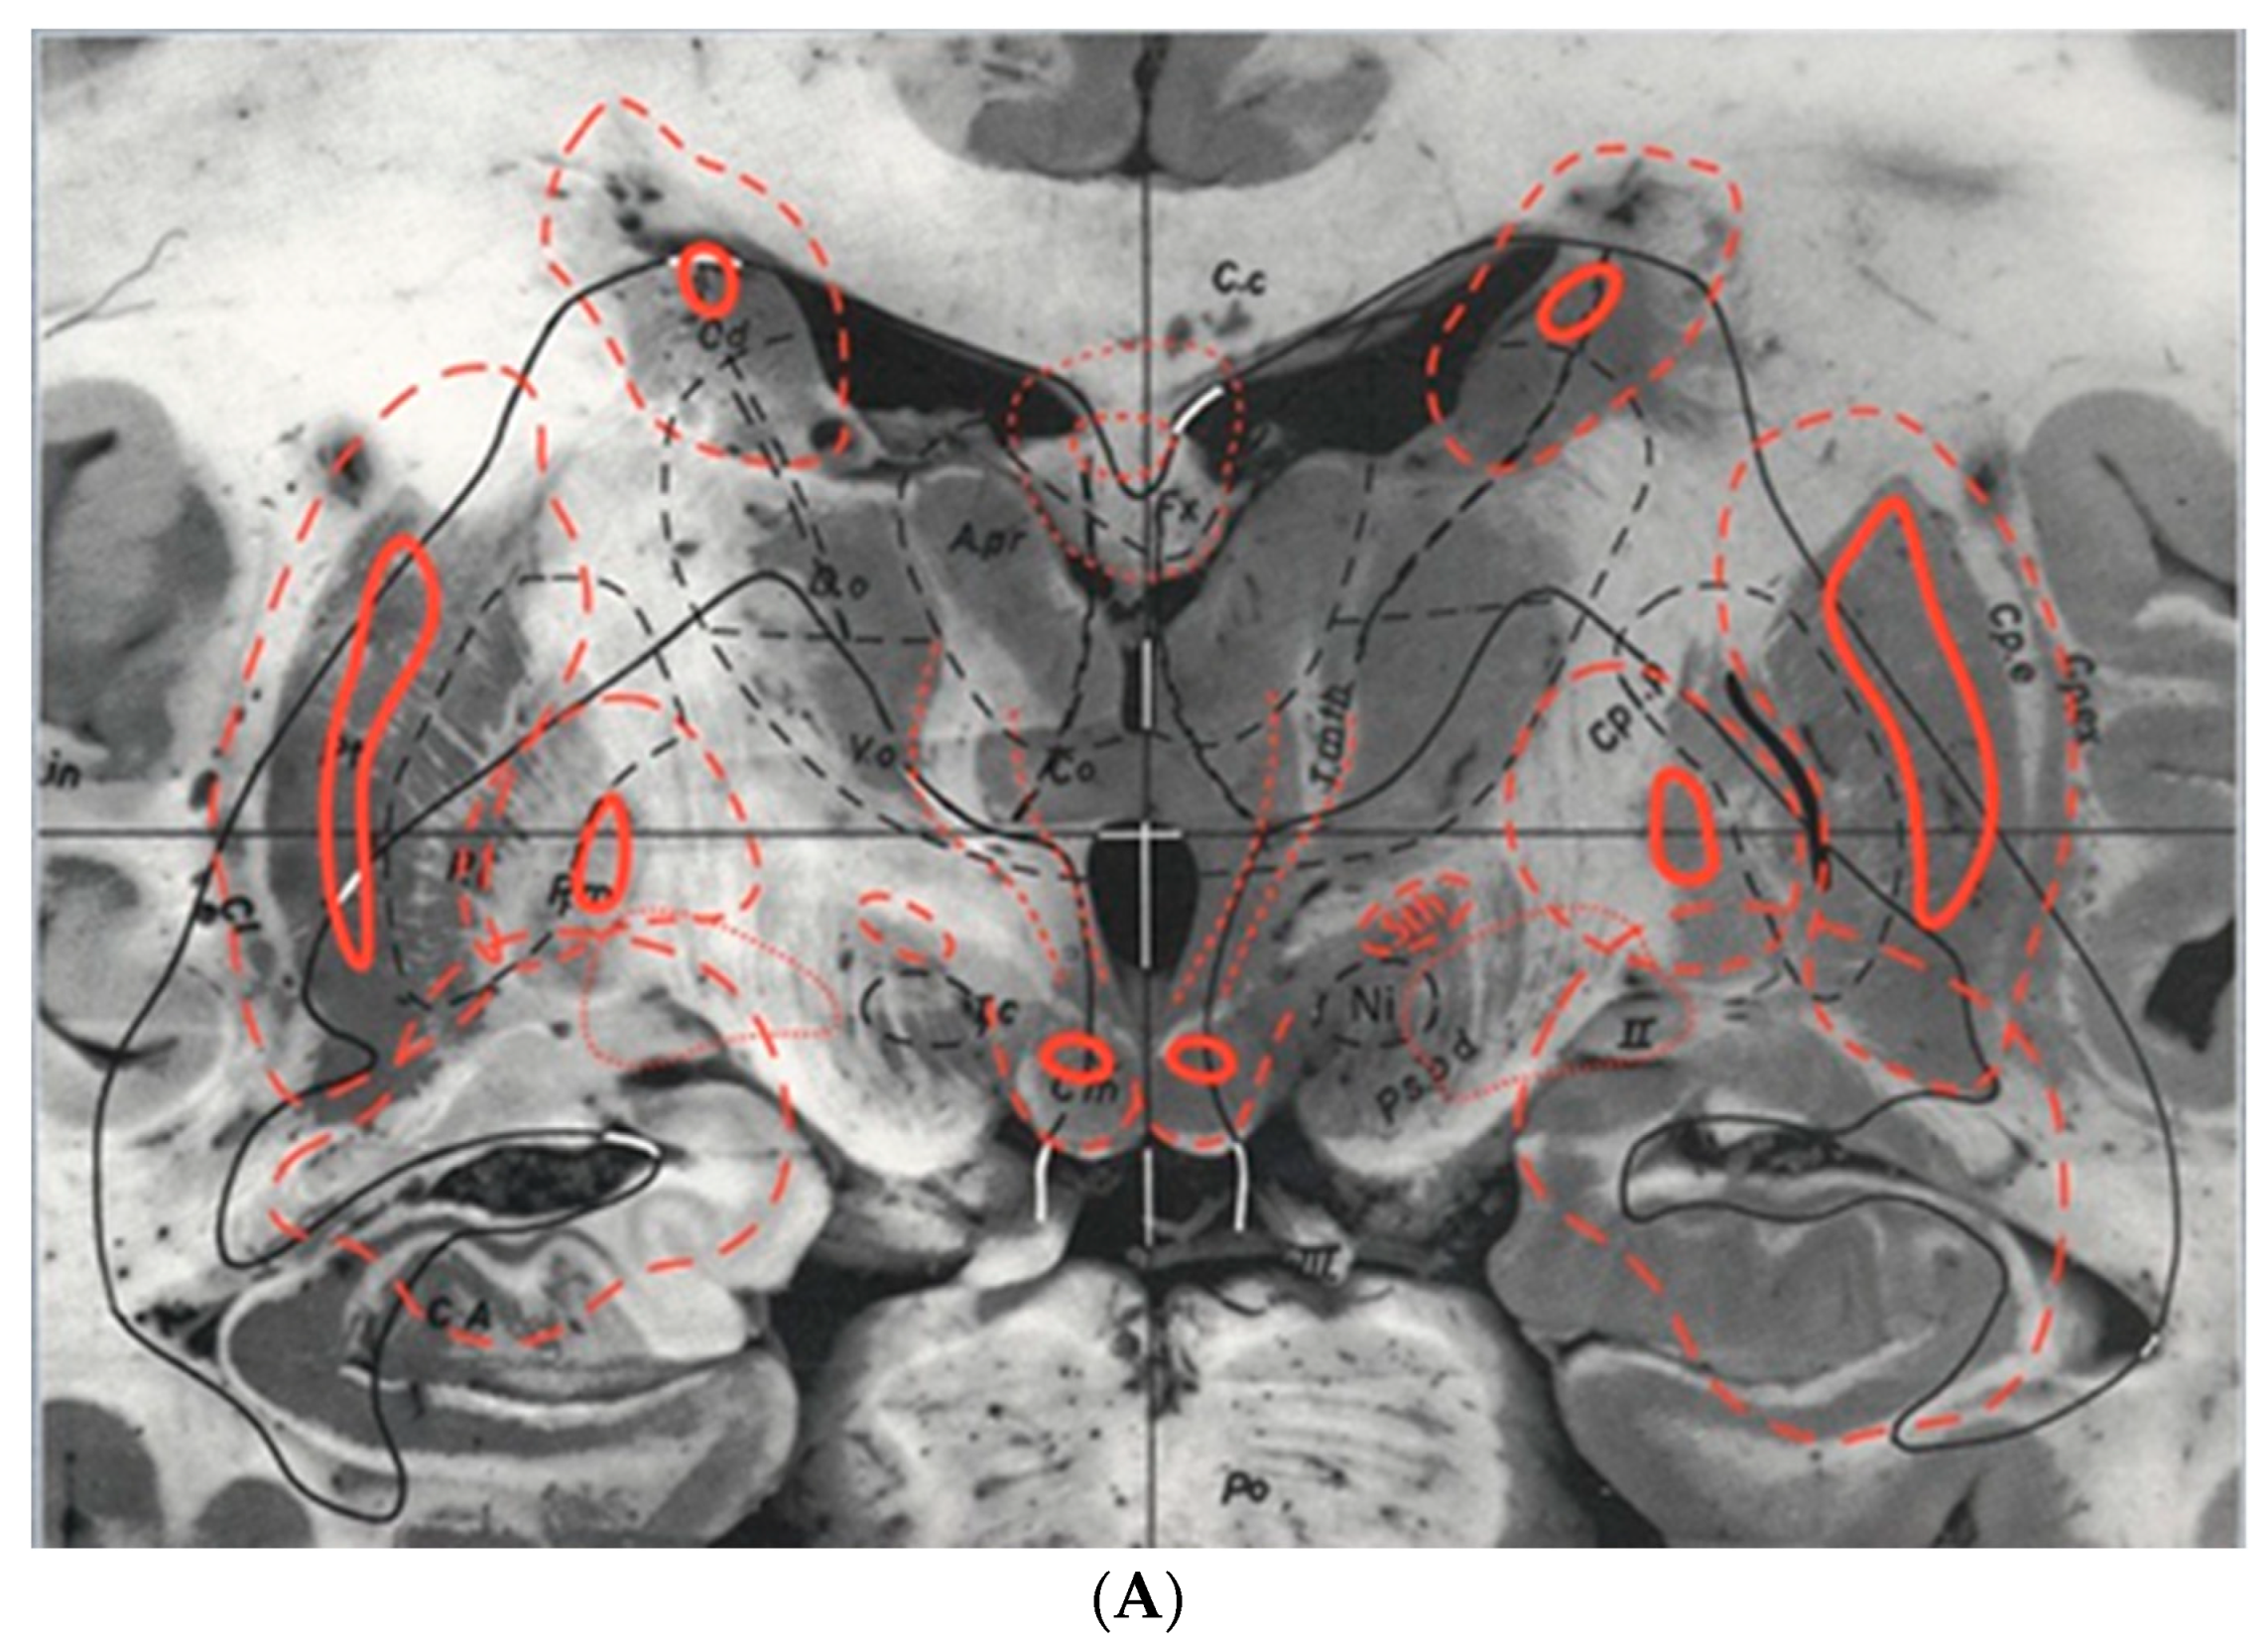

7.1. Consistencies and Inconsistencies of the Talairach and Tournoux 1988 and the Schaltenbrand and Wahren Atlases

- Niemann, K.; van Nieuwenhofen, I. One Atlas-Three Anatomies: Relationships of the Schaltenbrand and Wahren Microscopic Data. Acta Neurochir. 1999, 141, 1025–1038. [Google Scholar] [CrossRef] [PubMed]

- Nowinski, W.L.; Liu, J.; Thirunavuukarasuu, A. Quantification and Visualization of Three-Dimensional Inconsistency of the Ventrointermediate Nucleus of the Thalamus in the Schaltenbrand-Wahren Brain Atlas. Acta Neurochir. 2008, 150, 647–653. [Google Scholar] [CrossRef] [PubMed]

- Niemann, K.; Naujokat, C.; Pohl, G.; Wollner, C.; von Keyserlingk, D. Verification of the Schaltenbrand and Wahren Stereotactic Atlas. Acta Neurochir. 1994, 129, 72–81. [Google Scholar] [CrossRef]

- Nowinski, W.L.; Liu, J.; Thirunavuukarasuu, A. Quantification and Visualization of the Three-Dimensional Inconsistency of the Subthalamic Nucleus in the Schaltenbrand-Wahren Brain Atlas. Ster. Funct. Neurosurg. 2006, 84, 46–55. [Google Scholar] [CrossRef]